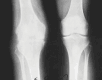

Musculoskeletal tuberculosis (TB) accounts for approximately 10% of all extrapulmonary TB cases in the United States and is the third most common site of extrapulmonary TB after pleural and lymphatic disease. Vertebral involvement (tuberculous spondylitis, or Pott's disease) is the most common type of skeletal TB, accounting for about half of all cases of musculoskeletal TB. The presentation of musculoskeletal TB may be insidious over a long period and the diagnosis may be elusive and delayed, as TB may not be the initial consideration in the differential diagnosis. Concomitant pulmonary involvement may not be present, thus confusing the diagnosis even further. Early diagnosis of bone and joint disease is important to minimize the risk of deformity and enhance outcome. The introduction of newer imaging modalities, including MRI (imaging procedure of choice) and CT, has enhanced the diagnostic evaluation of patients with musculoskeletal TB and for directed biopsies of affected areas of the musculoskeletal system. Obtaining appropriate specimens for culture and other diagnostic tests is essential to establish a definitive diagnosis and recover M. tuberculosis for susceptibility testing. A total of 6 to 9 months of a rifampin-based regimen, like treatment of pulmonary TB, is recommended for the treatment of drug susceptible musculoskeletal disease. Randomized trials of tuberculous spondylitis have demonstrated that such regimens are efficacious. These data and those from the treatment of pulmonary TB have been extrapolated to form the basis of treatment regimen recommendations for other forms of musculoskeletal TB.